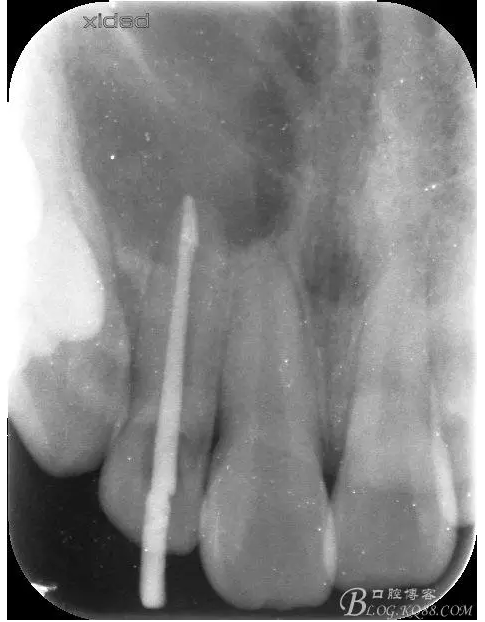

1.術(shù)前的根尖片檢查及根管治療影像:

圖2.根管治療術(shù)后直接局部 麻醉下切開(kāi)、翻瓣,發(fā)現(xiàn)12唇側(cè)骨壁有綠豆大小骨缺損

圖3.依缺損部位為中心,逐漸去骨,完整暴露出囊壁。